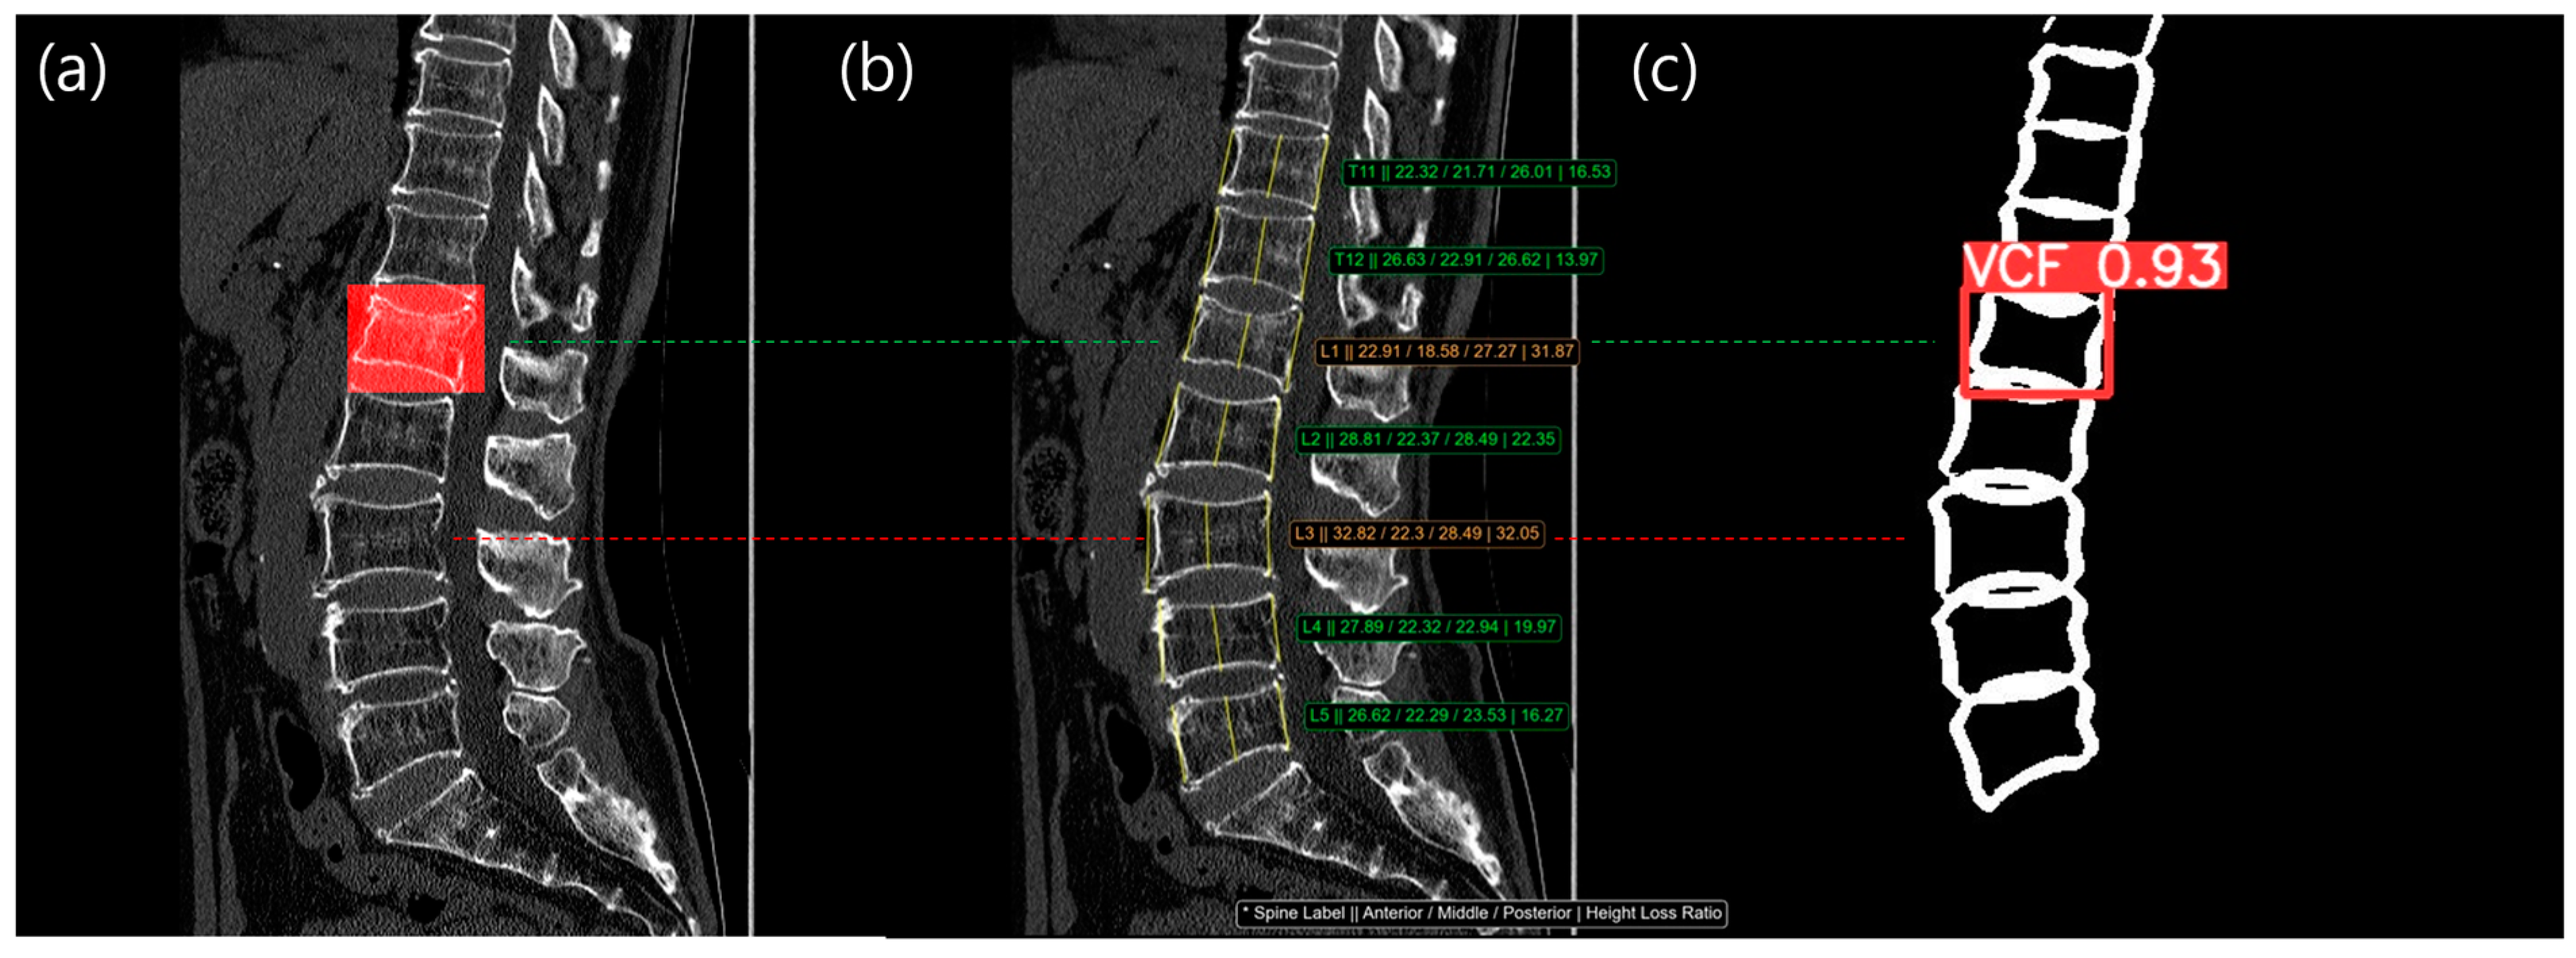

Figure 6 and Figure 7 showed example cases for Methods 3 and 4. The left image shows a filled red bounding box, representing the reference standard from a radiologist, overlaid on the patient’s CT images. The middle image shows the three main vertebral heights overlaid on the patient’s CT images. The right image shows the VCF detection result, with the confidence score overlaid on vertebral contour mask images. As shown in Figure 6, L2 and L4 were labeled as a VCF, but the HLR was normal, so it was not detected using method 1. However, the contour-based detection model was able to identify the VCF at L2 and L4 with a high confidence score (0.82 and 0.98, respectively), allowing Method 3 to detect the previously missed VCF case. In Figure 7, there was no red bounding box on the L3 vertebra, indicating that it was normal. However, the HLR of L3 was 32.05%, classifying it as a moderate VCF based on the Genant classification. The detection model also skipped L3, meaning Method 4 was able to identify more normal cases.

Figure 7.

The result images from our study are as follows: (a) Chronic VCF reference standard labeled by a radiologist; (b) HLR measurement, Method 1, result. The consecutive values in the image, indicated with an * symbol, were spine label, anterior height, middle height, posterior height, and height loss ratio.; (c) VCF detection, Method 2, result from vertebral contour analysis. At the L3 level (indicated by the red dotted line), the HLR was 32.05%, indicating a VCF. However, the VCF detection model did not identify the VCF. The green dotted line was TP in both Method 1 (b) and Method 2 (c). The red dotted line was FP in Method 1 (b) but TN in Method 2 (c).